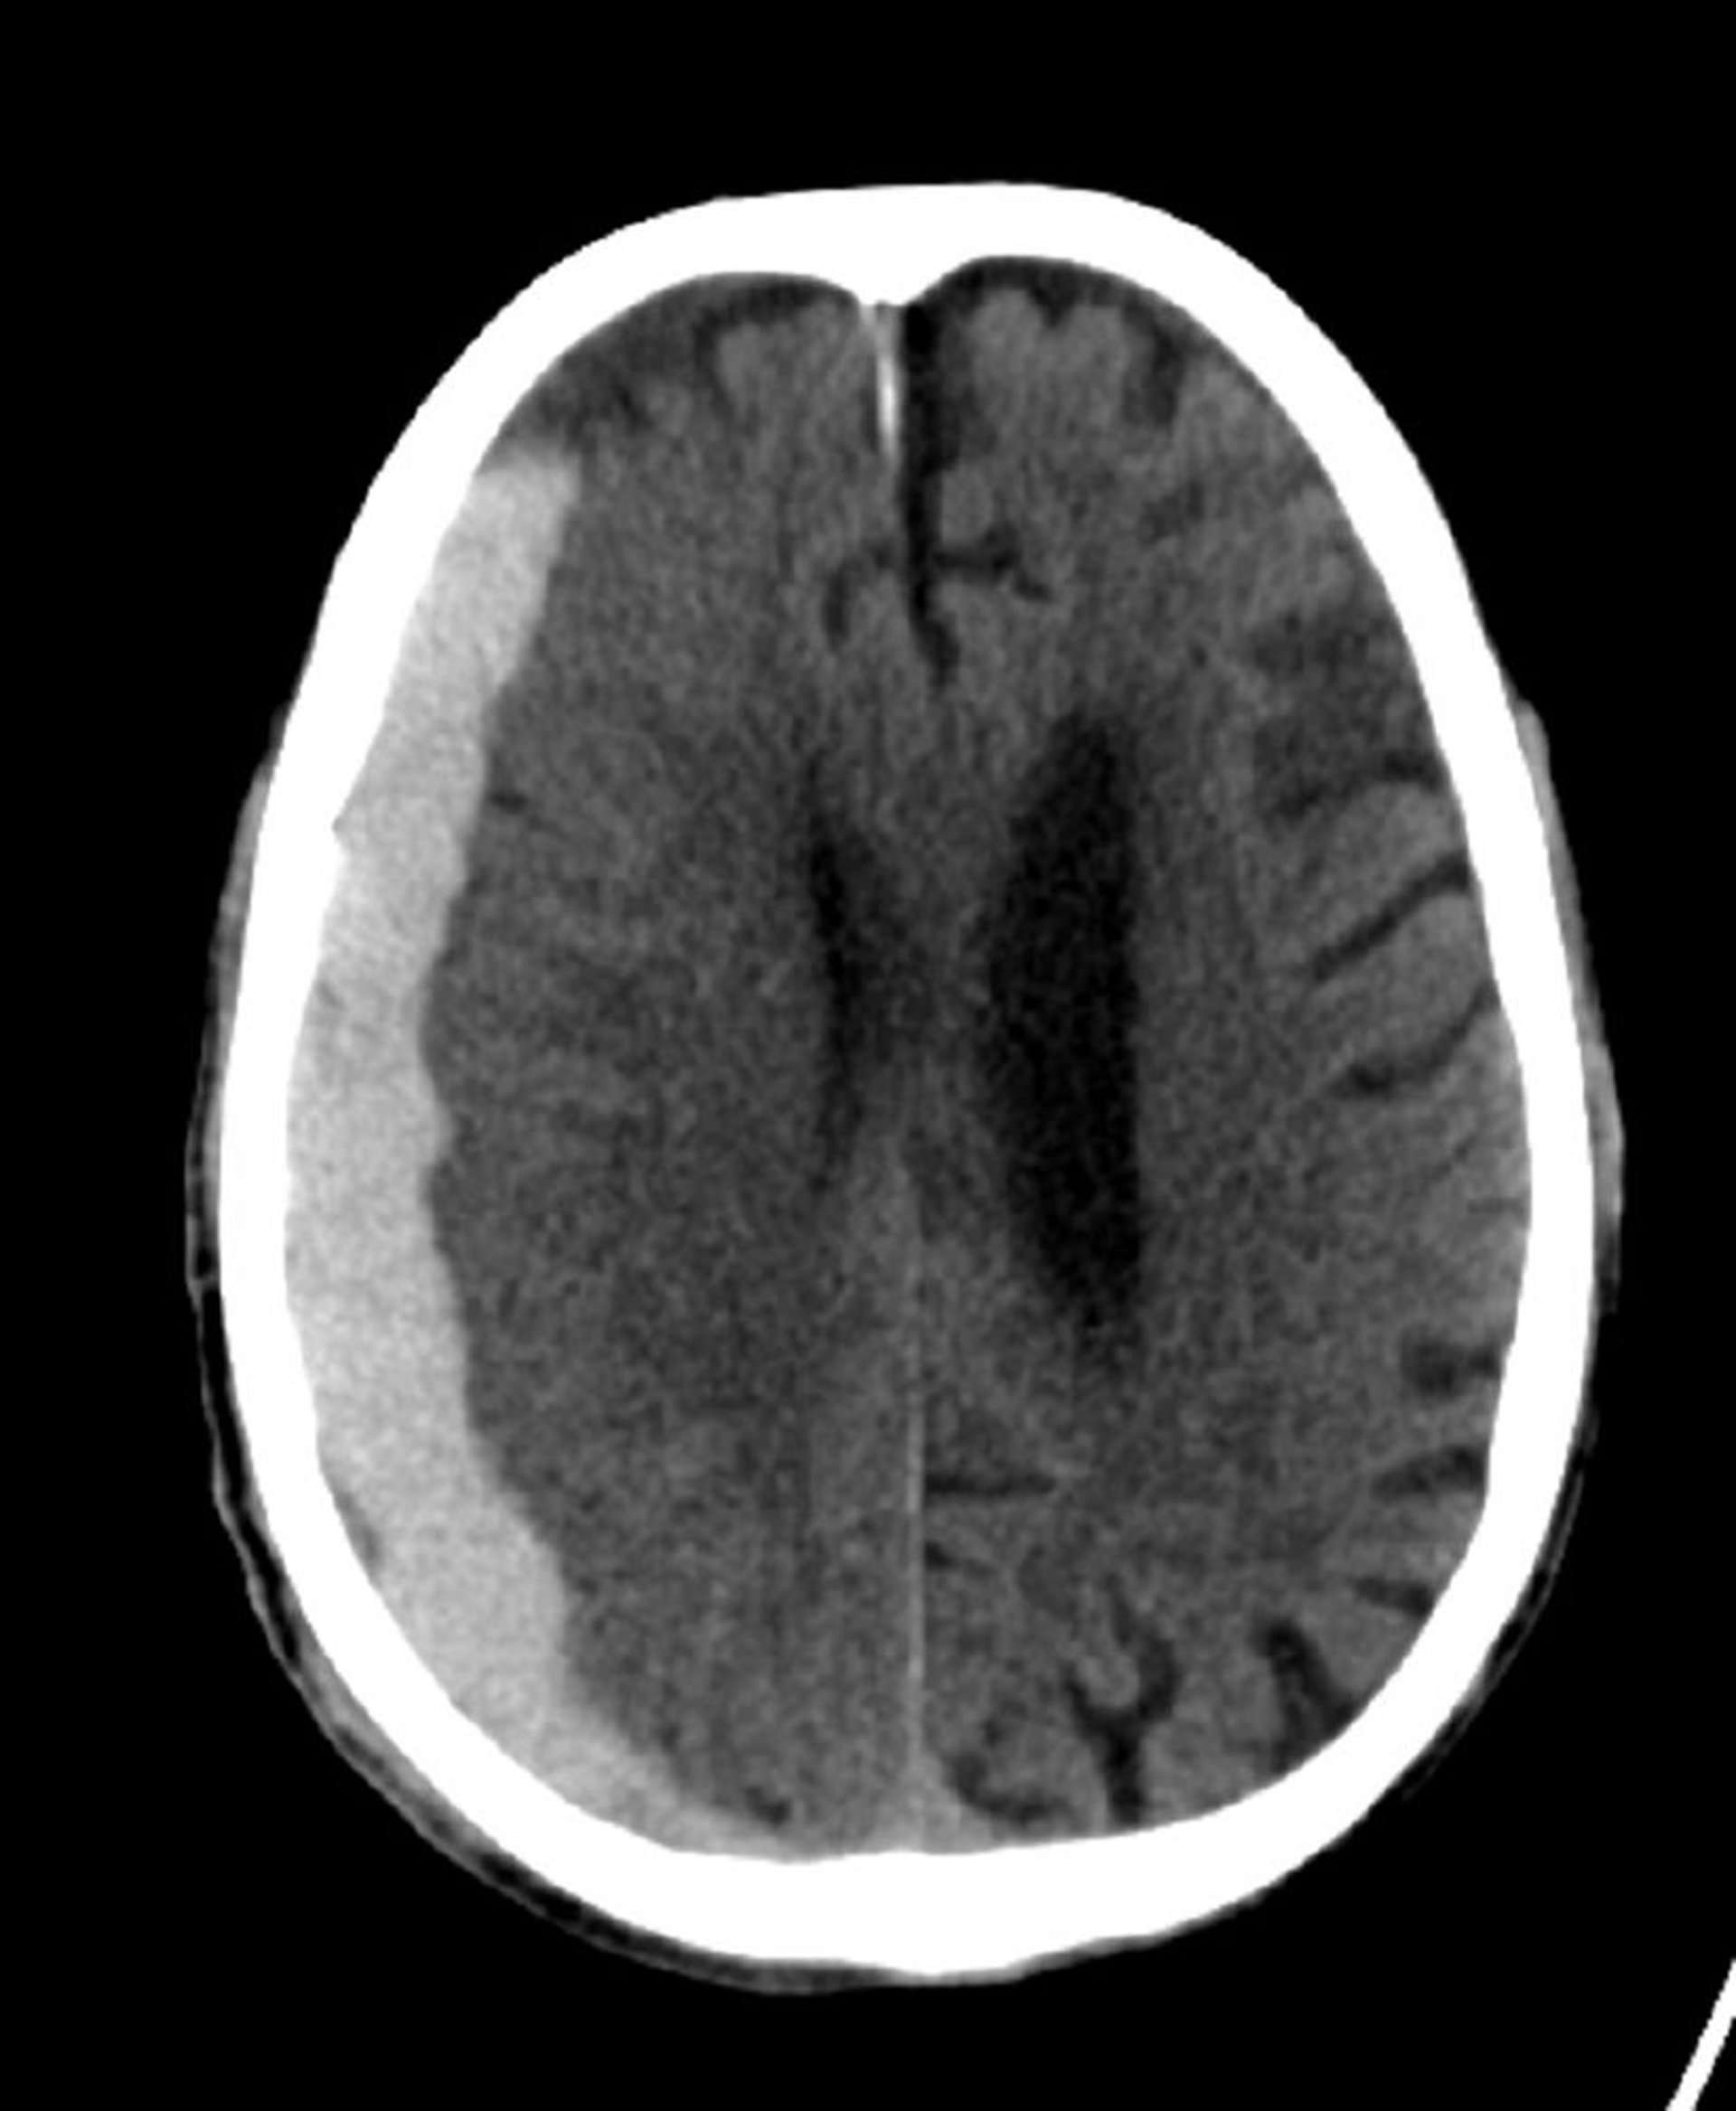

Hemorragia subdural (TC)

Hiperdensidad clásica en forma de medialuna que se extiende a través de las líneas de sutura.